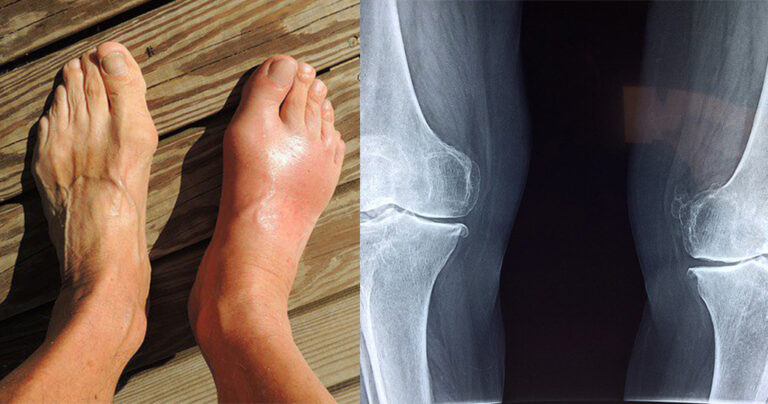

Τι είναι όμως η ουρική αρθρίτιδα; Είναι ένας τύπος αρθρίτιδας που προκαλεί φλεγμονή στις αρθρώσεις του σώματος και επηρεάζει συνήθως το μεγάλο δάχτυλο του ποδιού. Η ουρική αρθρίτιδα προκαλείται από την απόθεση κρυστάλλων ουρικού οξέος σε μια άρθρωση.

Οι εξετάσεις αίματος μπορεί να μην είναι πάντα ακριβείς. Έτσι, οι καλύτεροι τρόπο διάγνωσης είναι η υπολογιστική τομογραφία διπλής ενέργειας (dual energy CT-scan) και οι ακτίνες Χ.